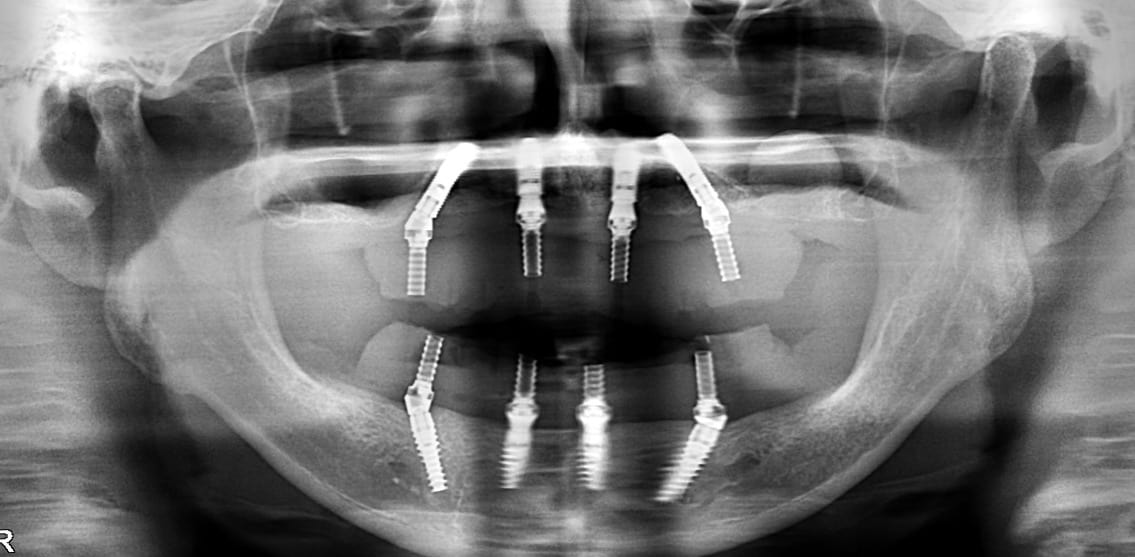

GUIDED SURGERY LIVE OPE SEMINAR ”All-on-4 × NOBEL GUIDE” co-sponsored by WHITE CROSS / NOBEL BIOCARE(2019.4.6SAT)